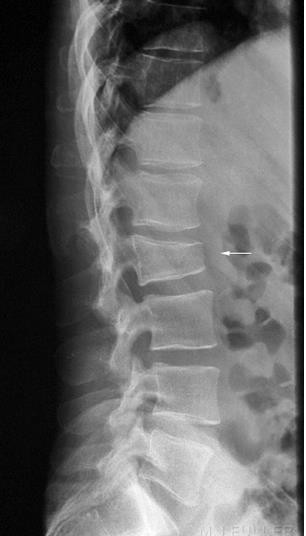

- Một số phương pháp chụp hệ xương khớp đặc biệt:

- Chụp cắt lớp vi tính: CT scanner (để chẩn đoán các loại u xương, gãy cổ xương đùi…)

- Chụp cộng hưởng từ MRI ( trong chấn thương cột sống, cổ xương đùi…)